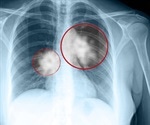

Lung Cancer News and Research

Latest Lung Cancer News and Research